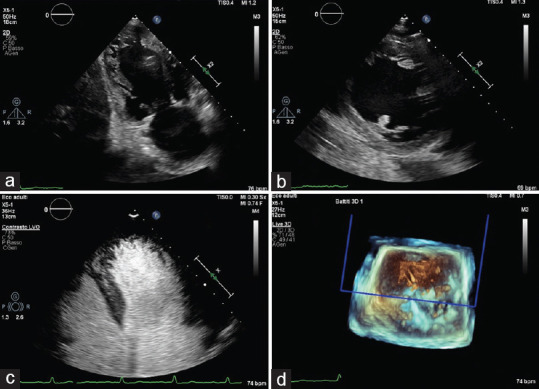

Left ventricular noncompaction (LVNC) is commonly described as a congenital cardiomyopathy characterized by prominent myocardial trabeculae and deep intertrabecular recesses extending in the left ventricular chamber. Clinical presentation can differ considerably from asymptomatic individuals to those presenting with heart failure and other serious complications. Diagnosis is usually made by two-dimensional transthoracic echocardiography or cardiac magnetic resonance. Moreover, even if strain parameters are significantly reduced in patients with LVNC, they are not routinely investigated. Here, we report the case of a previously symptomless patient admitted to the hospital for pulmonary edema. Two-dimensional transthoracic echocardiography showed severe valvular heart disease and left ventricle pronounced trabeculation and remodeling, although speckle tracking echocardiography (STE) demonstrated only mild strain reduction. We, therefore, explore the possibility that STE may be useful to differentiate LVNC cardiomyopathy from LVNC phenotype due to severe remodeling.